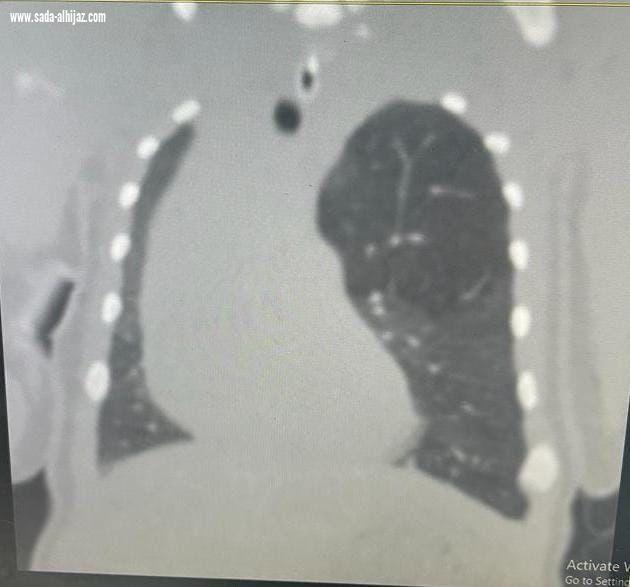

إستقبل مجمع الملك فيصل الطبي بالطائف حالة طفل خديج حديث الولادة يعاني من صعوبة في التنفس، وتم بشكلٍ عاجل عمل فحوصات وتحاليل وأشعة دقيقة للطفل أثبتت وجود تمدد بالفص الأيسر العلوي من الرئة، وتم تشكيل فريق طبي من عدة تخصصات شملت أطباء جراحة الصدر، وأطباء الرعاية الفائقة للأطفال الخُدج بالمجمع، وبعد دراسة الحالة تم اتخاذ قرار بإجراء جراحة عاجلة ودقيقة لاستئصال الفص الأيسر العلوي من الرئة عن طريق شق صدري محدود بمشاركة الدكتور نادر البرعي استشاري جراحة الصدر، والدكتور جاسر علي استشاري جراحة الصدر، والدكتورة عبير أحمد عبد السلام حسن طبيبة حديثي الولادة.

ووفقاً لما ذكرهُ متحدث صحة الطائف سراج الحميدان لـ "سبق"، فقد استغرقت الجراحة ساعتين وتحسنت الحالة الصحية للطفل بشكلٍ ملحوظ، وخرج المريض من المستشفى بعد أيام من العملية بدون مضاعفات بفضل الله.